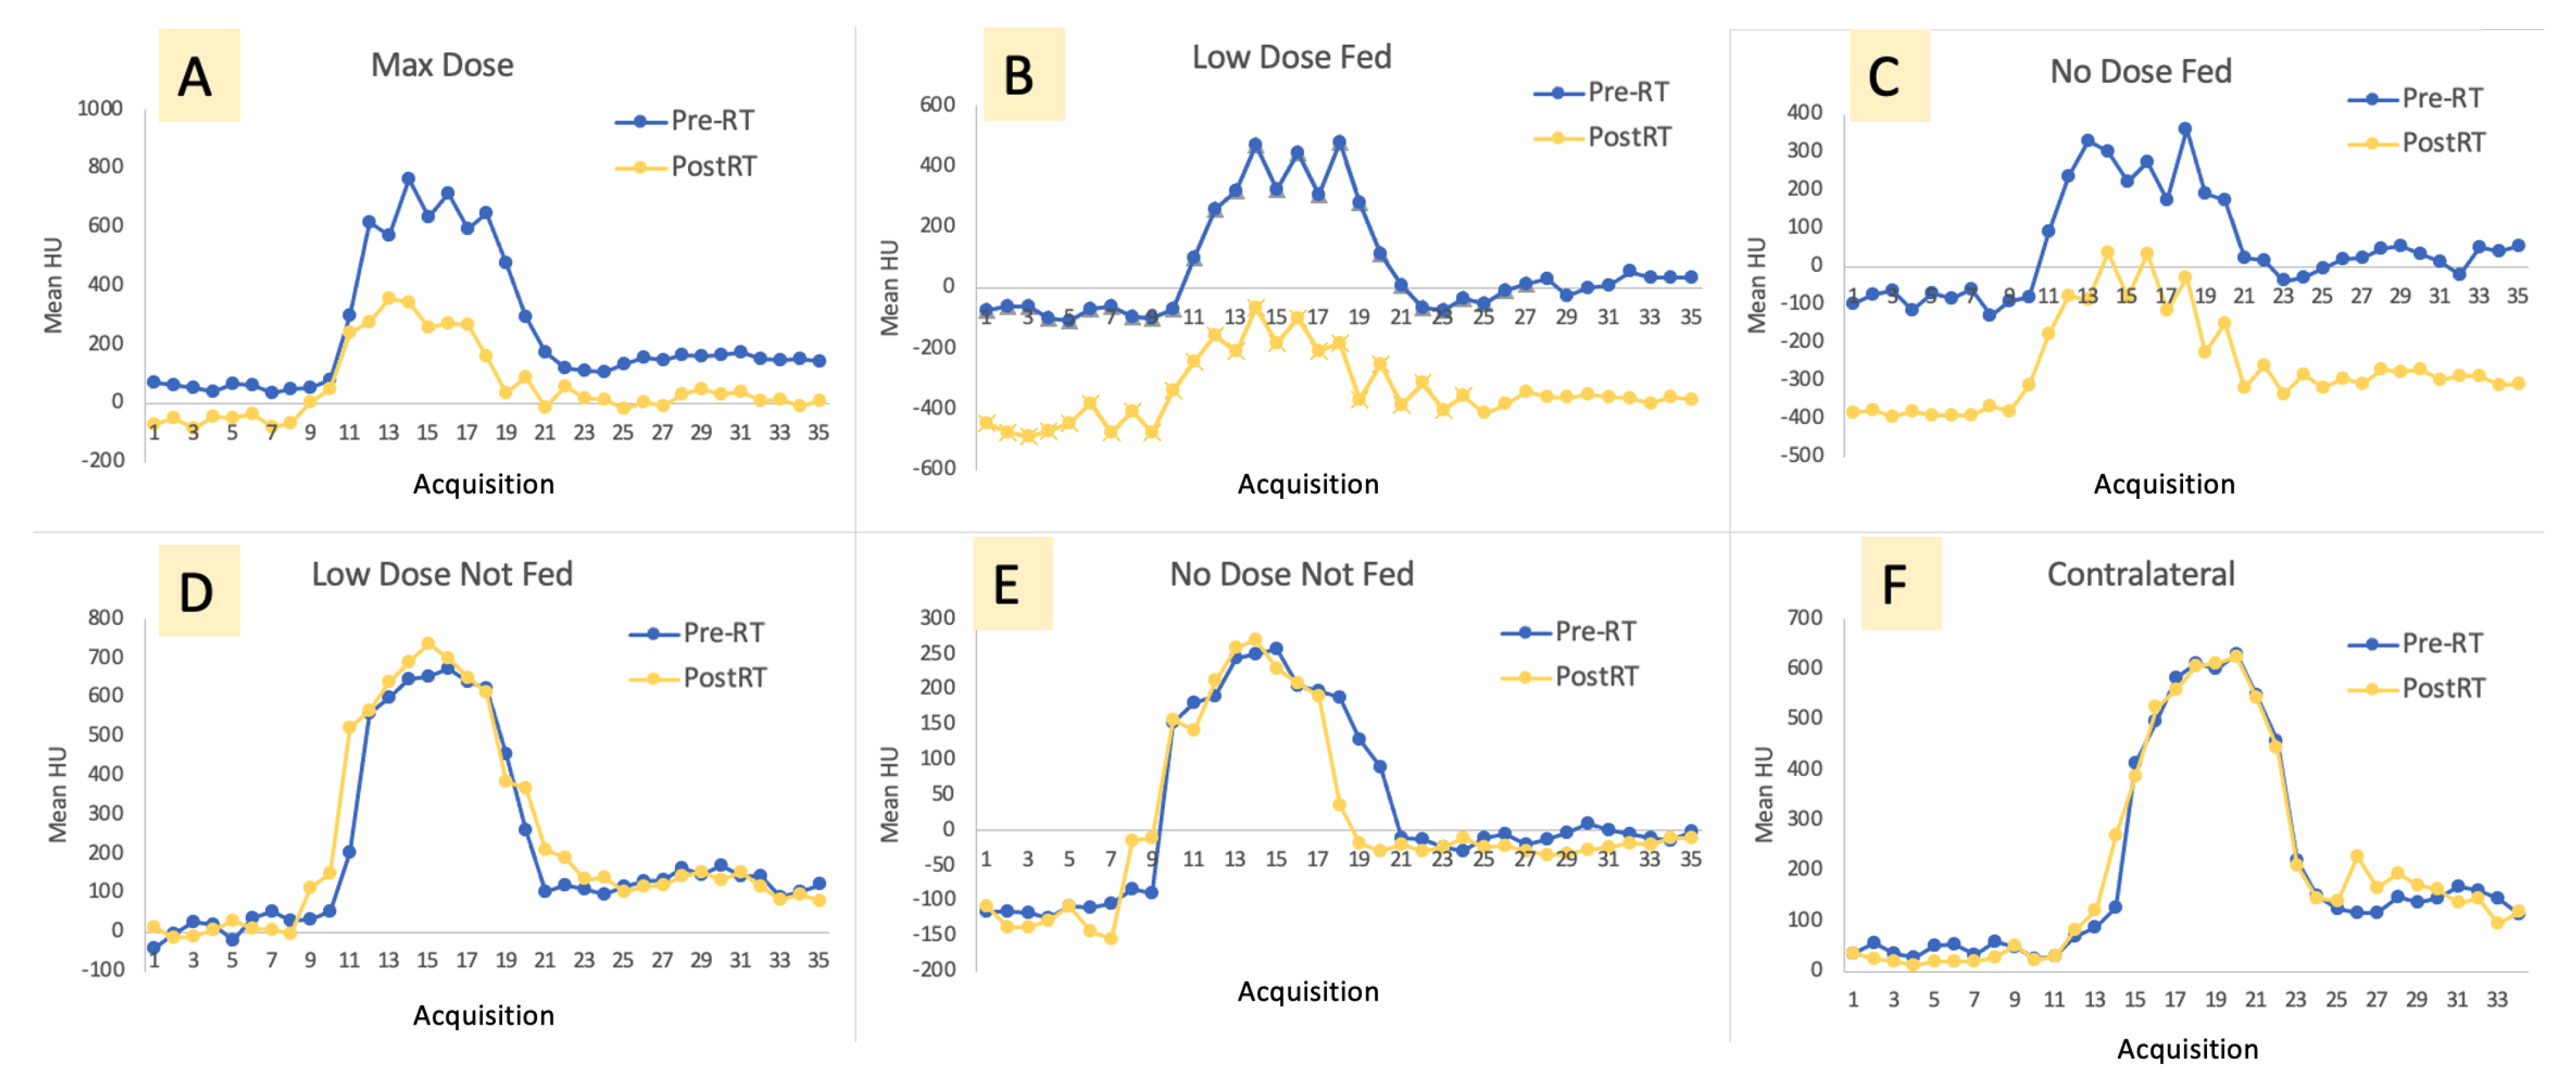

3. Results

Imaging Results

4.1. Changes in Kinetics

4.1.1. Ipsilateral Contours

4.1.2. Contralateral Lung

| Max Rise | Max Value | Baseline to Baseline Time | Baseline to Baseline Difference | Slope Up | Slope Down | Area under Curve | |

|---|---|---|---|---|---|---|---|

| Max Dose (Ipsilateral) | −40.7% (16.1%) * | −41.7% (18.1%) * | −26.3% (16.8%) * | −68.5% (23.1%) * | −43.0% (16.3%) * | −47.1% (19.2%) * | −56.0% (21.0%) * |

| Low-Dose Fed (Ipsilateral) | −42.6% (33.4%) * | 13.6% (201.6%) | −3.9% (32.9%) | −125.0% (99.1%) | −47.7% (34.0%) * | −66.4% (25.9%) * | −65.0% (24.0%) * |

| No-Dose Fed (Ipsilateral) | −28.4% (47.8%) | −128.1% (232.6%) | −20.8% (32.0%) | −32.7% (9.7%) * | −50.6% (33.3%) * | −36.7% (42.4%) * | −55.0% (27.0%) * |

| Low-Dose Not-Fed (Ipsilateral) | −24.3% (52.6%) | −14.9% (68.8%) | −9.7% (43.9%) | −46.9% (41.0%) | 80.3% (212.4%) | −38.6% (41.4%) | −36.0% (54.0%) |

| No-Dose Not-Fed (Ipsilateral) | −32.0% (32.0%) | −29.4% (35.3%) | 3.1% (38.4%) | −47.7% (18.0%) * | 79.9% (160.1%) | −1.3% (91.8%) | −24.0% (23%) |

| Contralateral | 5.8% (15.2 %) | 2.0% (12.1%) | −3.2% (33.2%) | −3.1% (5.0%) | 40.5% (114.9%) | 17.9% (40.1%) | −5.0% (25.0%) |